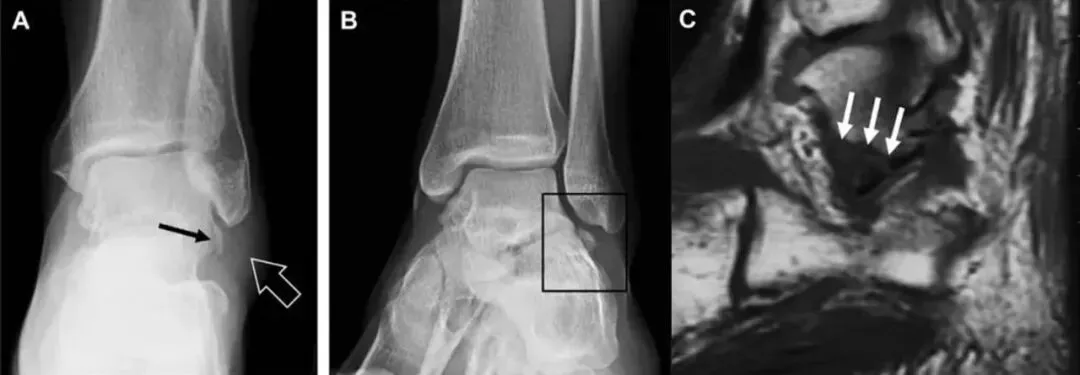

(如图)距骨外侧突骨折。

A-正位片示内翻损伤所致的距骨外侧突撕脱性骨折(箭头)。

B-另一位患者,踝外翻损伤导致典型的[滑雪板者骨折],X 片上可见一较大的三角形骨折块(方框)。

C-第二位患者的 MRI 矢状位 T1 加权像示横行骨折(箭头)。